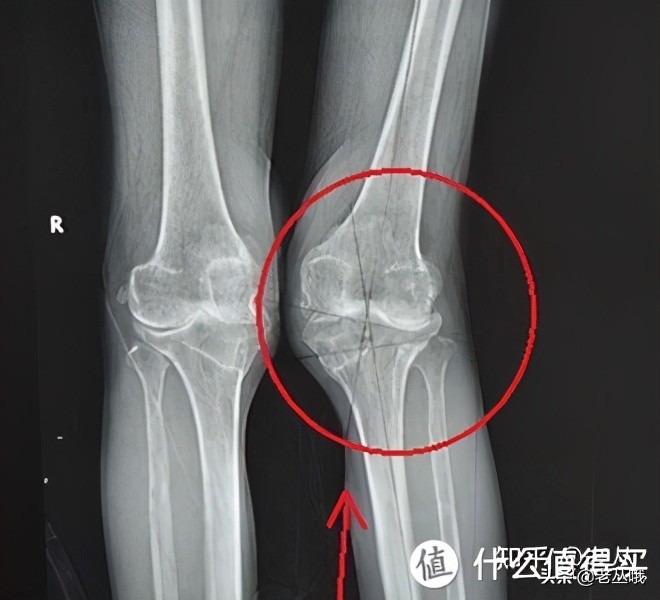

你说这是不是x型腿?

不要以为膝盖挨一起,大腿小腿有空隙就是x型腿好不啦?

自查:这叫x型腿,x型腿不是一般人能拥有的,造吗?

1.大腿自然并拢,双脚无法触碰

2.膝盖指向过于向内

3.足外翻

如果以上三种情况,有2-3点你都满足,就可以确定是x型腿。

如果只满足1点都无法判断,就是这么严谨奥!!

1、首当其冲就是关节损伤

膝盖过于内扣,整个膝关节处于不稳定、不平衡的状态,增加了半月板磨损、肌肉韧带拉伤的风险。